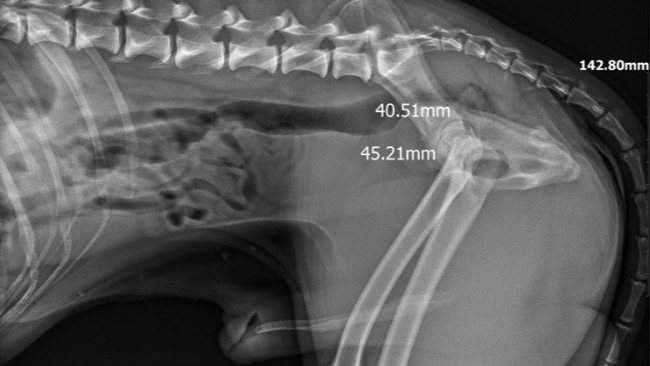

Objawy Barrego mają silnie wyrażony charakter, pies od początku jest diagnozowany klinicznie i obrazowo, jednak nadal nie postawiono konkretnej diagnozy. Proponowane są kolejne, badania, zabiegi… A Barry, dzień po dniu, traci władze w swoich tylnich kończynach. To jednak, nie przeszkadza panu Markowi sprawować nad nim opieki na najwyższym poziomie i nie poddawać się w walce o ukochanego przyjaciela. Potrzebujemy pieniędzy na dalsze działania i rozwikłanie tej zagadki. Barry na chwile obecną potrzebuje rezonansu magnetycznego kręgosłupa z badaniami PMR. Chciałybyśmy aby właściciel nie musiał wybierać między swoim zdrowiem, a życiem swojego psa…

Ciągle przyjmowane leki, liczne wizyty weterynaryjne, fizjoterapeutyczne. To i tak zbyt mało w ogniu rosnących kosztów. Fizjoterapia widocznie wspiera Barrego i jego właściciela, ale aby móc działać celowanie i kompleksowo- musimy wiedzieć co odbiera Barremu władze w nogach!